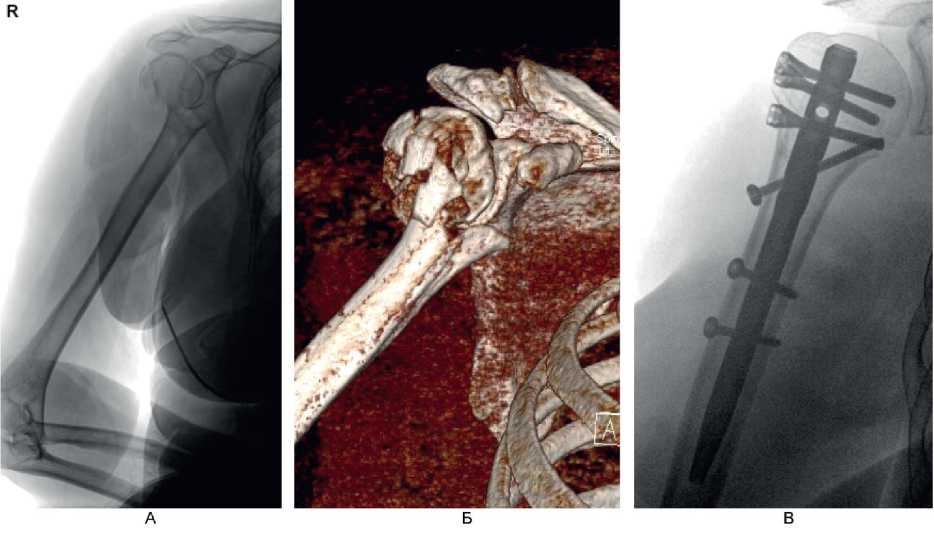

На контрольном осмотре через 6 мес у 7 (63,6 %) пациентов этой группы отмечено полное восстановление функции в плечевом суставе, у 4 (36,4 %) больных – небольшое ограничение движений и боль при движениях. Клинический пример 1. Больная М., 60 лет, поступила во ВЦЭРМ им. А.М. Никифорова в экстренном порядке. При поступлении выполнены рентгенография плечевого сустава в стандартных проекциях (рис. 6А) и компьютерная томография (см. рис. 6В). Перелом по классификации АО – В3. На 2-е сутки после поступления выполнено оперативное вмешательство – БИОС перелома хирургической шейки правой плечевой кости (см. рис. 6В).

Рис. 6. Больная М., 60 лет. А – рентгенография; Б – компьютерная томография поврежденного сегмента конечности; В – контрольная рентгенография в 1-е сутки после операции (косая проекция)

Функциональный результат через 6 мес после операции показан на рис. 7.

Рис. 7. Больная М., 60 лет. Функциональный результат через 6 мес после операции